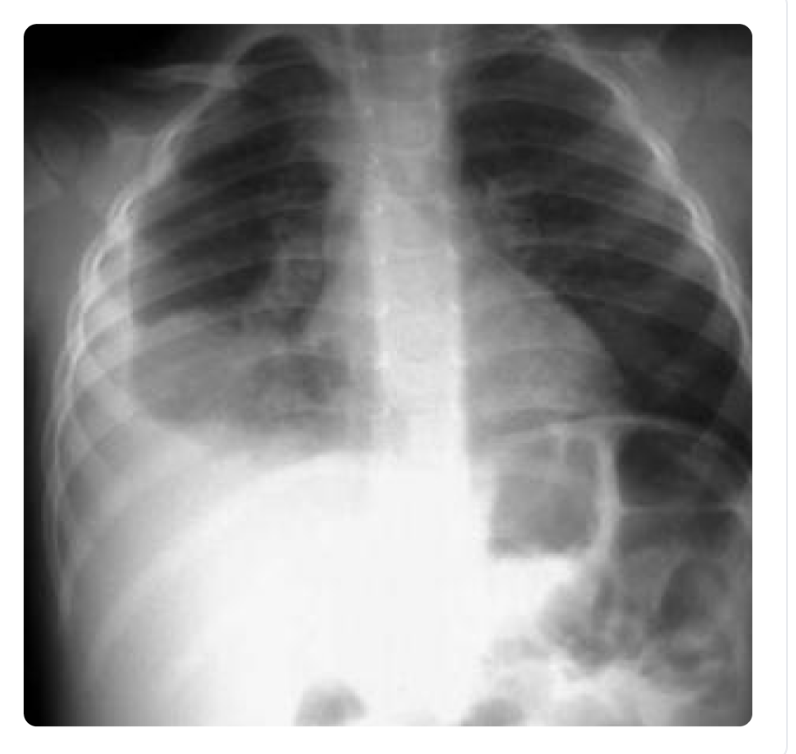

_______ is associated with meconium aspiration syndrome in the newborn

persistent pulmonary hypertension